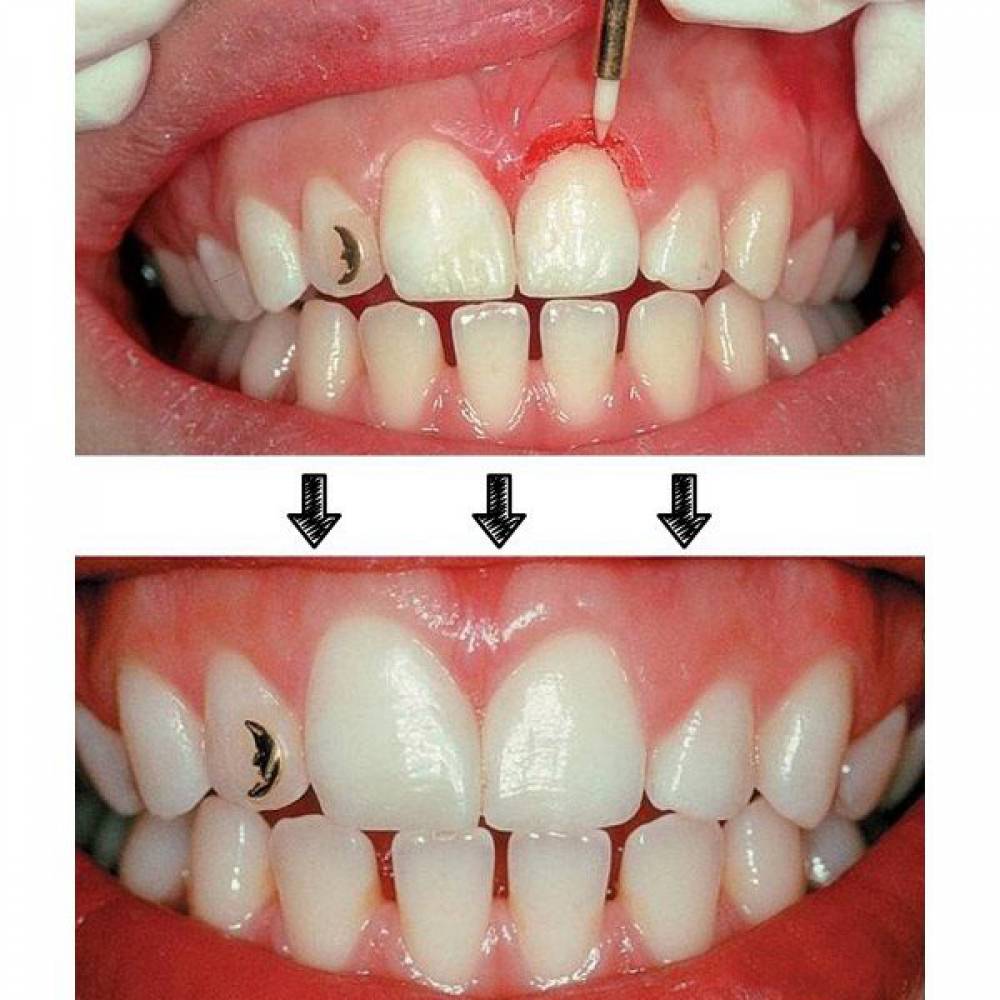

- کاربرد : برداشت لثه (Papilectomy) - برداشت بافت هاى مزاحم نشست روکش - باز کردن سالکوس قبل از گرفتن قالب - آشکار سازى بخش هاى از ایمپلنت که دیده نمى شود و دندانها نهفته

- ویژگی ها : انرژى جنبشى در بافت نرم به حرارت تبدیل مى شود .